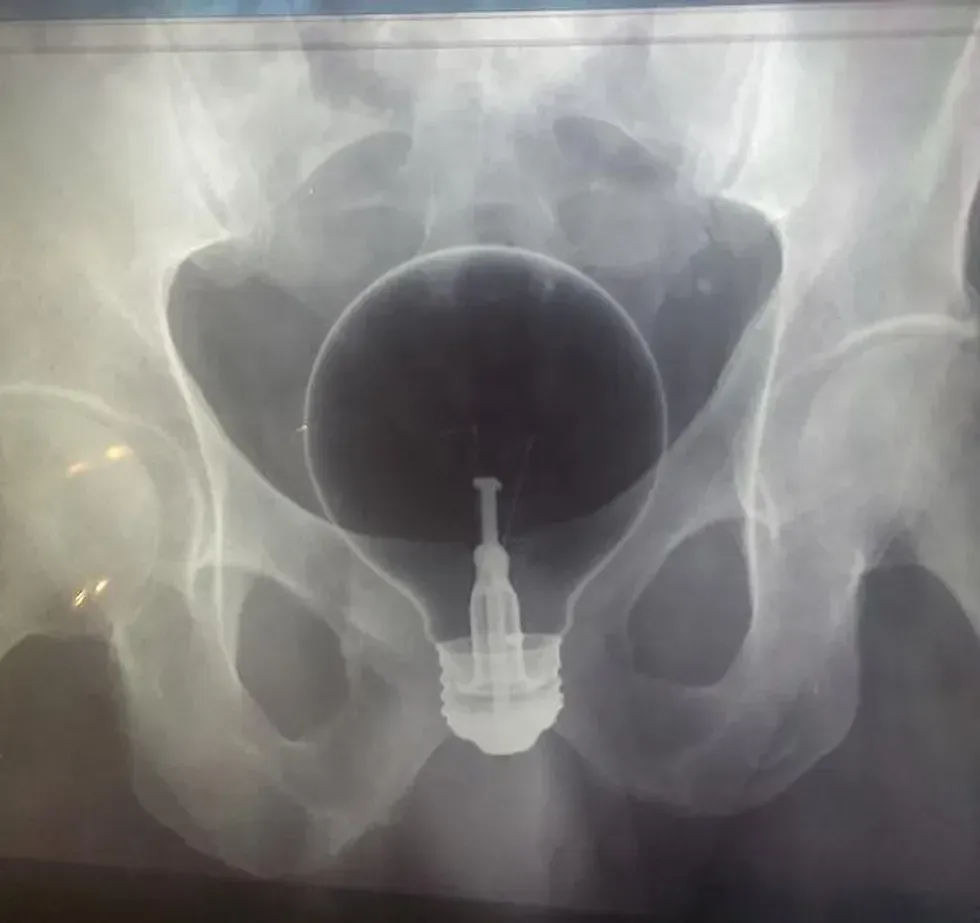

12. A light bulb